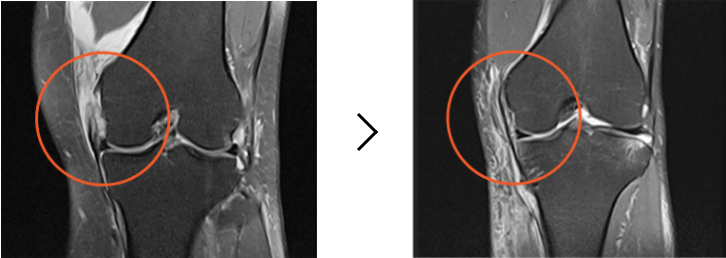

수술 전 : 끊어진 부위가 하얗게 보임(MRI)

수술 후 : 끊어진 부위를 봉합하여 연결함(MRI)